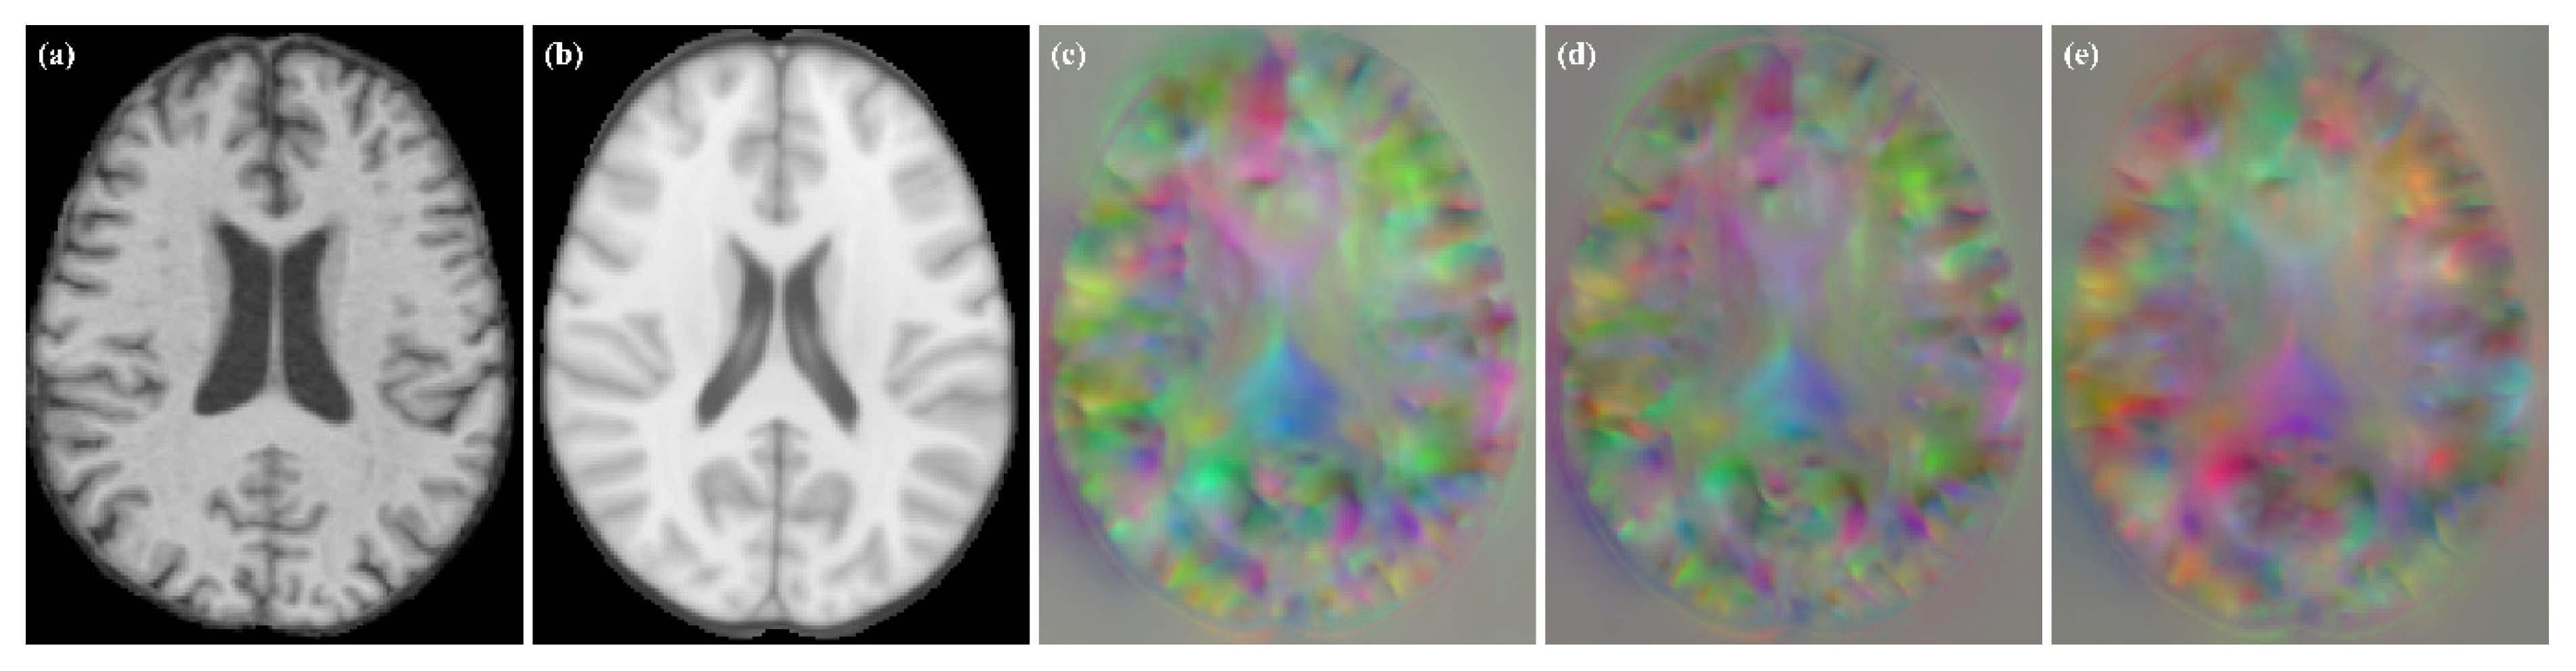

To verify the robustness of the method, we tested it on VoxelMorph and Label-reg models. The experimental results are shown in Figure 9. We found that we obtained DDF without grid-like artifacts under different models.

Figure 9.

Moving image, fixed image and DDFs obtained for different models. (a) moving image; (b) fixed image; (c) VoxelMorph; (d) VoxelMorph (JD); (e) Label-reg.